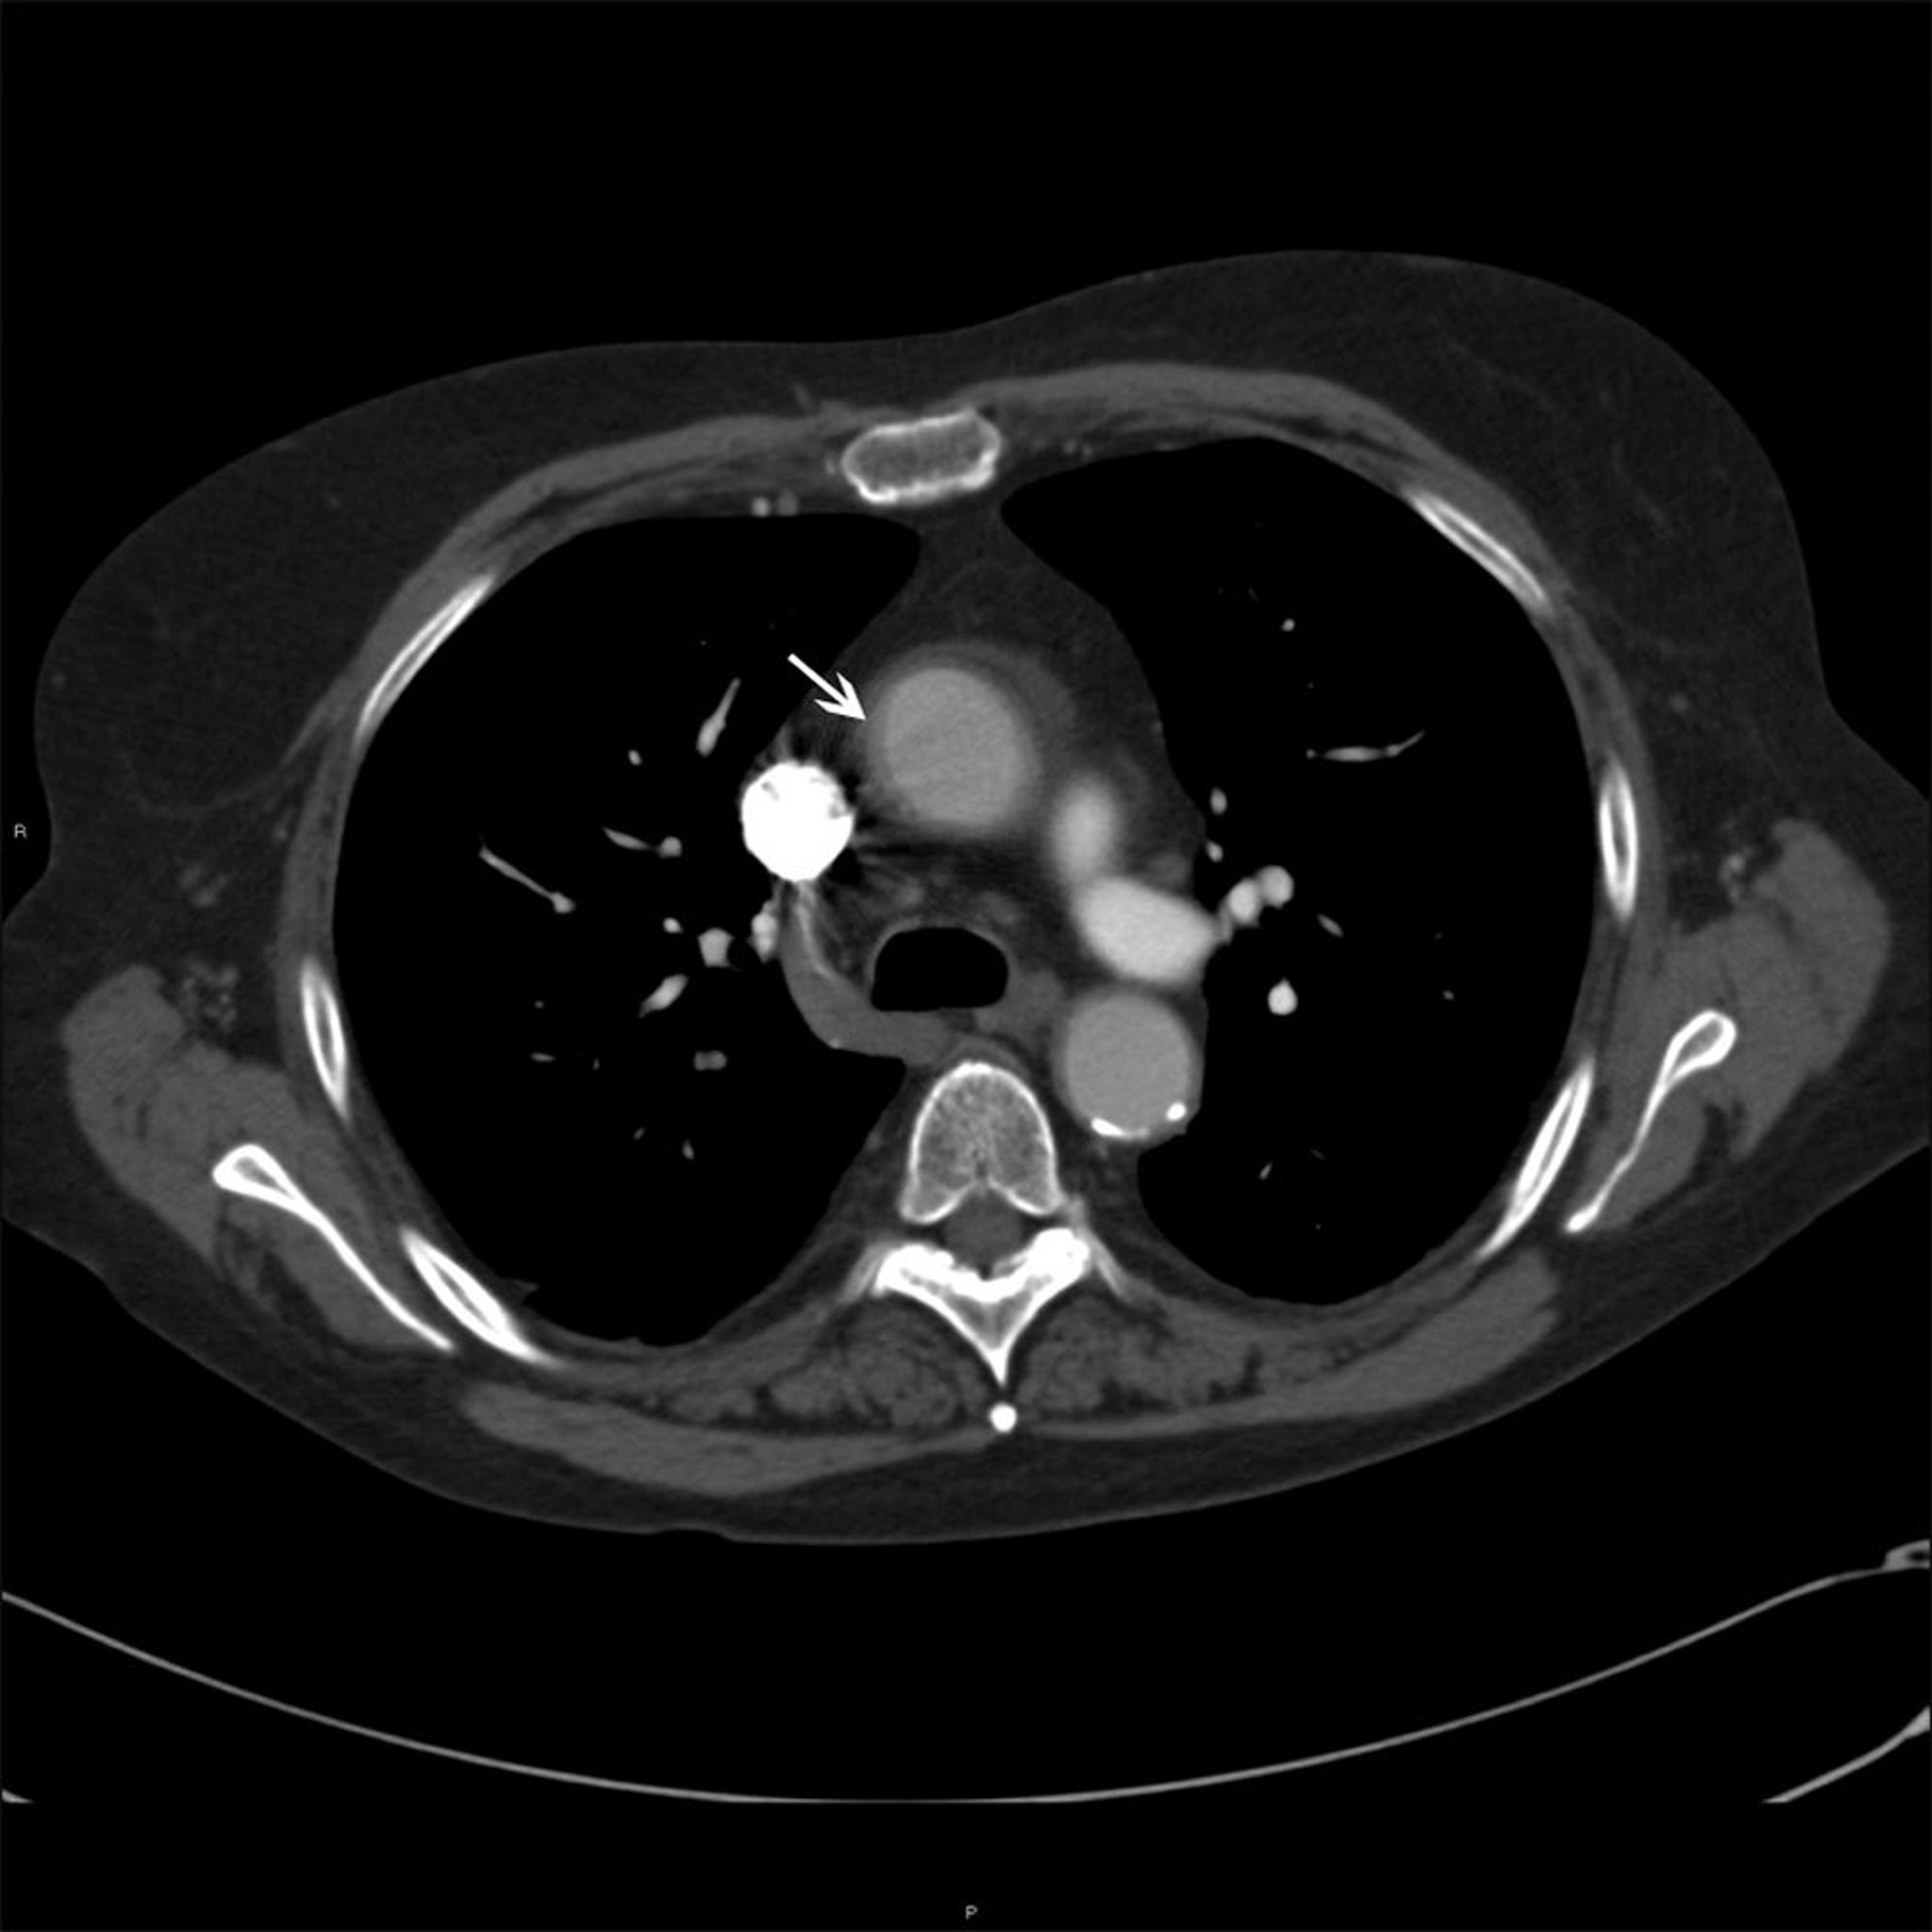

Восходящий отдел аорты у пациента с артериитом Такаясу

На этой фотографии показано утолщение стенки (белая стрелка) восходящей аорты у пациента с артериитом Такаясу.